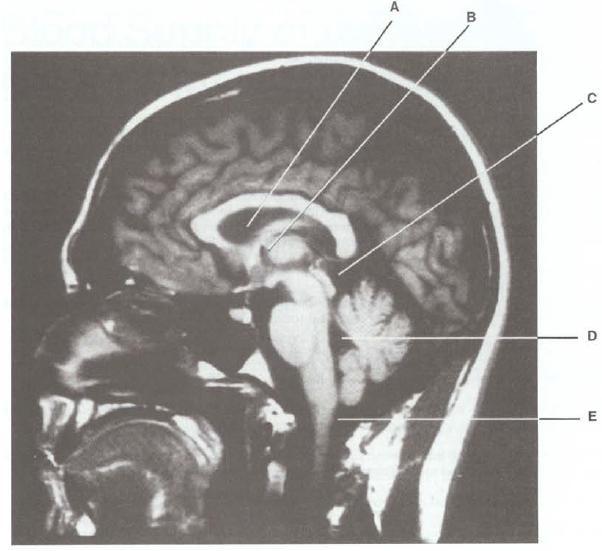

MAtch each letter with the appropriate T1-weighted MRI below

1. Olive

2. It contains the trochlear nerve (CN IV)

3. Its stenosis results in hydrocephalus

4. Contains a calcified glomus

5. Receives cerebrospinal fluid (CSF) from

the arachnoid villi

8-E. The olive is a prominent surface structure of the medulla.

9-D. The ambient cistern contains the trochlear nerve (CN IV).

10-C. Stenosis of the cerebral aqueduct prevents cerebrospinal fluid (CSF) from entering the

fourth ventricle; this results in a noncommunicating hydrocephalus.

11-B. The trigone of the lateral ventricle contains a large tuft of choroid plexus called the glo-

mus. It is usually calcified and highly visible in computed tomography (CT) images.

12-A. The superior sagittal sinus receives cerebrospinal fluid (CSF) via the arachnoid villi.